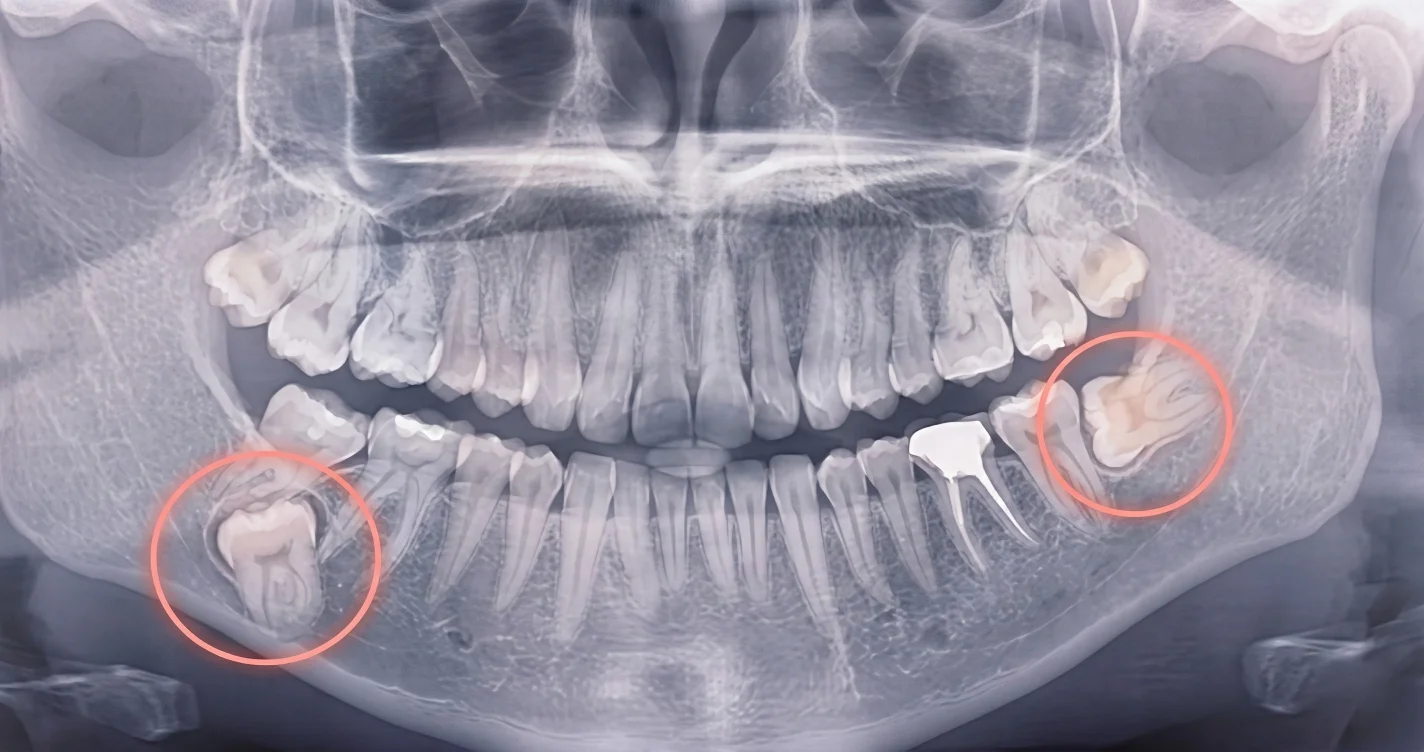

Базовый инструмент — ортопантомограмма (ОПТГ (4): показывает все зубы и зачатки, видно положение и угол. Для планирования лечения нужна компьютерная томография (КТ (5) — точное 3D-положение, отношение к корням соседей, глубина в кости. Первый снимок ребёнку рекомендуется в 6–8 лет.

Базовый инструмент — ортопантомограмма (ОПТГ, панорамный снимок). Показывает все зубы и зачатки, видно положение и угол. При любом подозрении на ретенцию — ОПТГ обязательна.

Для планирования лечения нужна компьютерная томография (КТ, 3D-снимок). Она показывает точное пространственное положение: нёбно или щёчно, насколько близко к корням соседей, как глубоко в кости. Согласно систематическому обзору Ravi et al (2021), КТ существенно точнее панорамного снимка для планирования хирургического этапа. Ravi et al., 2021